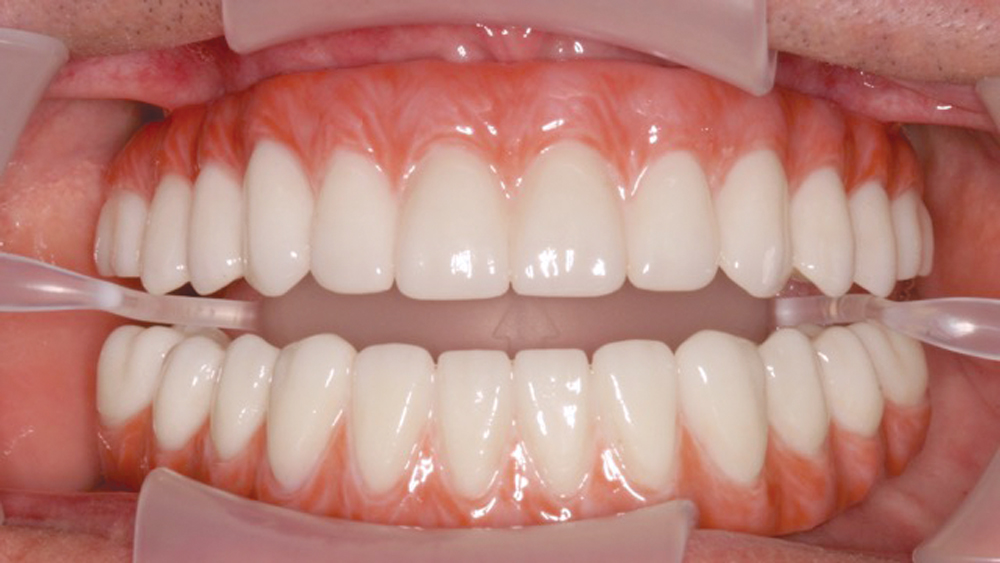

Once osseointegration is complete, the BruxZir® Full-Arch Implant Prosthesis is the ideal choice for the restoration, as its monolithic construction prevents chips, stains, breakage, and dislodged or worn-down prosthetic teeth.3,4 This treatment option has helped elevate the quality of care I’m able to provide for my edentulous patients, who no longer return to my office with a broken acrylic appliance in hand.

The following case demonstrates how to immediately place implants in full-arch indications. By properly positioning the implants, maximizing primary stability and providing the most durable restoration possible, the short- and long-term needs of the patient are addressed in an efficient, predictable manner.

For patients with adequate quantity and quality of bone, extraction with immediate implant placement is an efficient means of tooth replacement that reduces the number of surgical procedures and shortens the duration of treatment. In full-arch indications, this approach can deliver results that instantly transform dental form, function, personal confidence and quality of life. Achieving a predictable, long-lasting result has been simplified by innovations in implant design and prosthetics, making this an excellent option for practitioners providing implant therapy for their terminal dentition or edentulous patients.